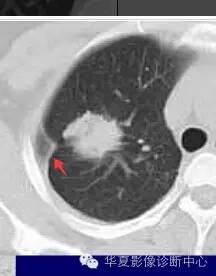

如果不看边缘是否清楚,就好像癌肿

但是一看边缘就是炎性病变

大家记住了,边缘模糊的GGO首先考虑炎症

磨玻璃结节良恶性影像分析策略磨玻璃结节良恶性影像分析策略 这个按常规看到血管由凹陷处进去常规95%考虑癌,可是这里却不是

除非说这里GGO边缘稍模糊一些